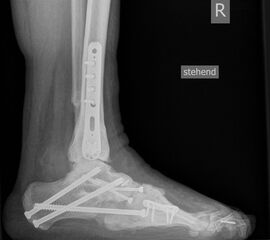

• posttraumatisch (Abb. 5)

• Fuß belastet dp und seitlich (Abb. 14 und 15)

• Saltzman view (Abb. 16)

Zum Lesen der Bildbeschreibung und zur Vollansicht bitte die Bilder anklicken. Bilder: A. Simon

b) Ergänzende Röntgendiagnostik

• Oberes Sprunggelenk ap und seitlich

• Gehaltene Aufnahmen des Sprunggelenks bei Verdacht auf Instabilität 6